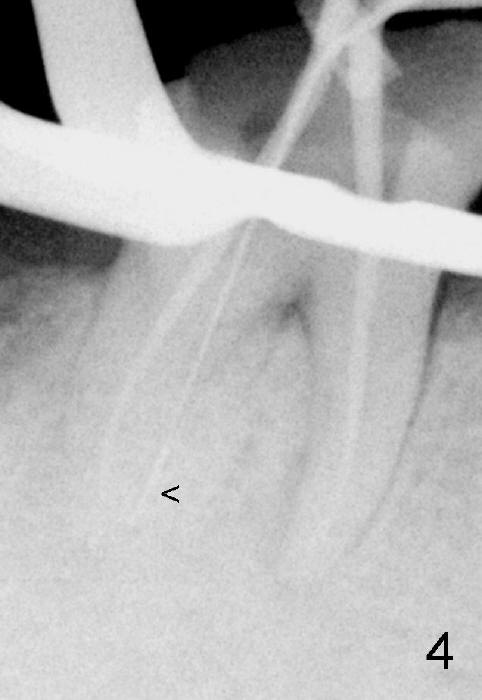

五十来岁郑先生缺失两个下颌第二磨牙,严重牙齿磨耗,三年前主诉右下第一磨牙冷热痛(可能与磨耗有关),近中有轻度根尖阴影(图一箭头),初步CT检查表明该牙齿有四个根管(图二,三),兴高采烈,这样不会错过远中舌侧根管(DL),开髓发现根管几乎阻塞,尤其是远中舌侧,hand files不容易进入根尖,使用20/.04 rotary file时,在根尖断裂(图四箭头,其余根管插入30/.06牙胶尖),一时不能bypass断针,暂封。十二天后,重新bypass断针,终于成功,但是取不出断针,扩大二十号hand file(远中舌侧根管),图五,图六侧方充填(lateral condensation)之前,图七之后(图六,七*:近中阴影)。根管治疗和牙冠之后一直无症状,一年半在第二磨牙处植牙(图八I),虽然第一磨牙近中根尖阴影增大(*),但离植牙还有一定距离,可能不会产生问题。不过不久植牙松动,病人自己取出,可能当时钻洞太大,而不够深(no primary stability),怕侵犯下颌神经(图八红线)。十个月后再次试图植牙(图九D:钻头),突然发现智齿(阻生)在手术视野之中,而且智齿咬合面不干净,结果取消植牙,把智齿拔除,这时病人第一磨牙仍没有症状,但是根尖阴影不可观(图九*),远中舌侧根尖好像没有病变(箭头)。大概这次智齿拔除也与左下智齿七拔除(左下第二磨牙植牙之前)一样不舒服,郑先生一直没有回来做右下第二磨牙植牙。上周六他终于登门,右下第一磨牙出现根尖脓肿症状(术后近三年),根尖片如图十。S代表已经愈合智齿牙槽窝,根尖阴影不小,断针根尖仍没有阴影。